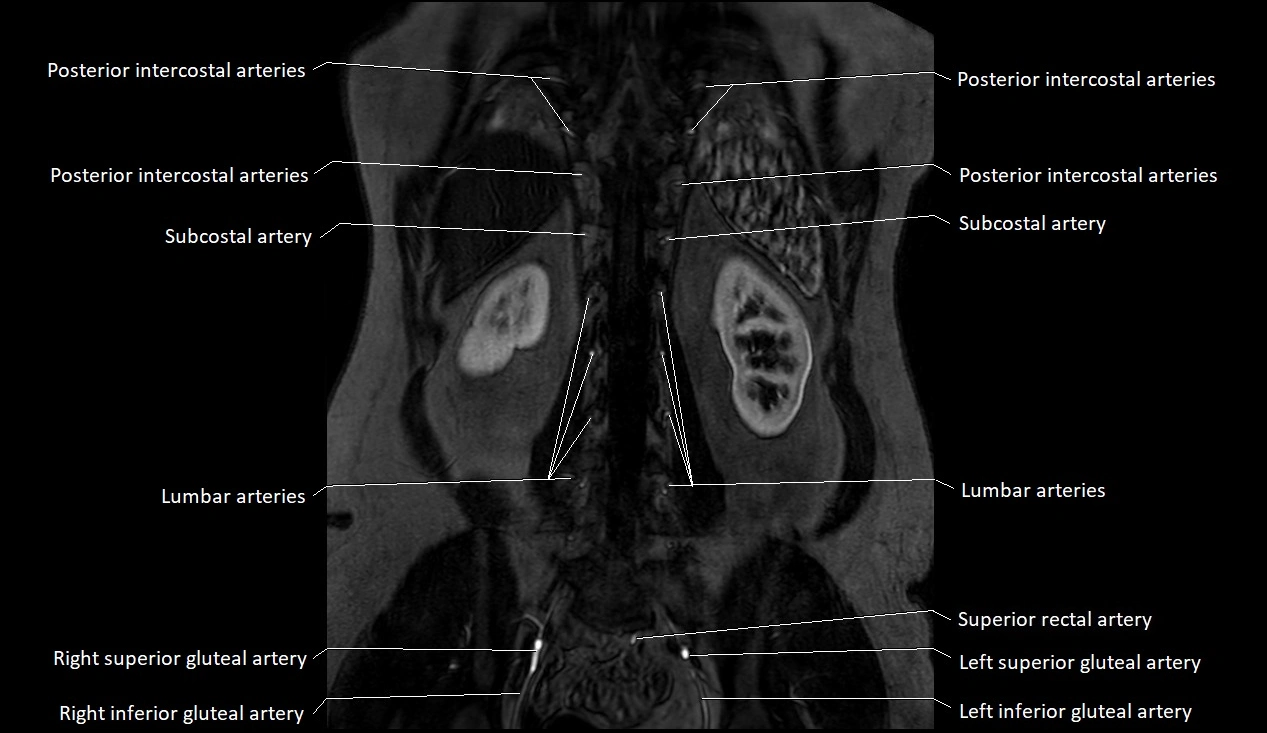

MRA (Magnetic Resonance Angiography):

• Contrast-enhanced MRA provides high-resolution imaging of the aorta and its branches

• Allows 3D reconstruction of visceral, parietal, and terminal branches

• Excellent for evaluating aneurysm size, dissection flap, stenosis, or preoperative planning

• Non-invasive alternative to conventional angiography

MRI images

image